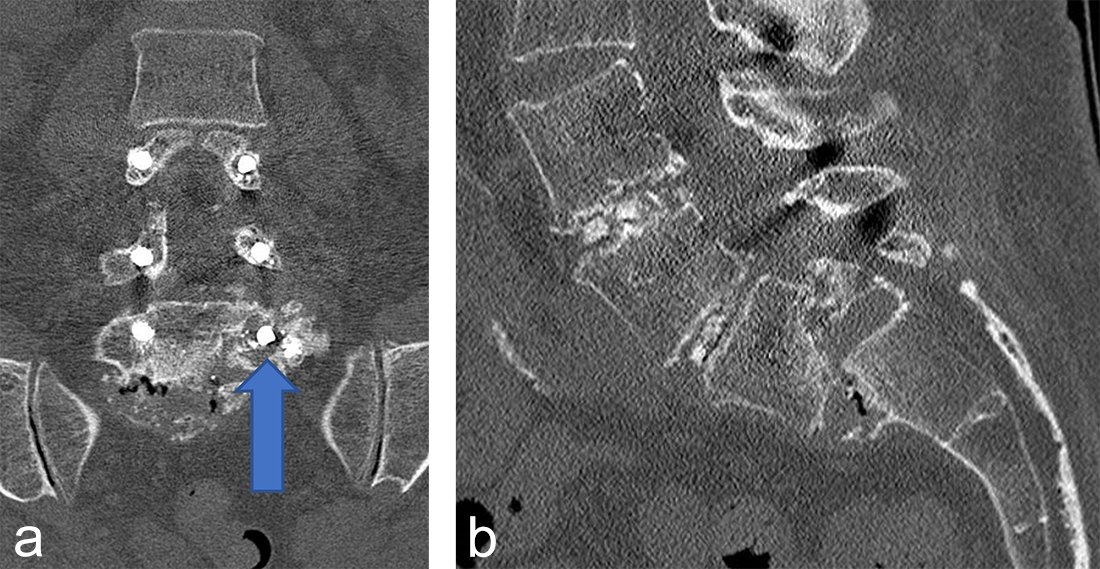

Two other patients had cement leakage into the neuroforamen which caused motor and sensory dysfunction of the affected nerve root. In retrospect the chosen screw length was too short for the vertebra; therefore, the most posterior located perforation in the screw was located within the pedicle (Fig 2).

Instrumentation failure occurred in 7 (11.5%) of 61 patients. One patient developed loosening of the three most caudal nonaugmented screws in a long fusion construct. Two patients had screw loosening after a proven infection (one of them with augmented screws). One developed screw loosening due to a pedicle fracture. Another had CAPS loosening after traumatic fracture of the L5 vertebral body (Fig 3). Two patients had a screw breakage. In total 3 (0.86%) of 233 cement- augmented pedicle screws in 61 patients failed despite cement augmentation (Table 2).